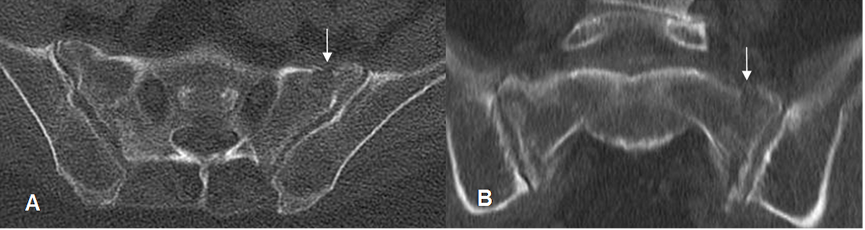

Fig 69. Fractura de stress.

A: TAC axial y B: TAC reconstrucción coronal. Signos de osteopenia, con fractura longitudinal en el alerón del sacro del lado izquierdo.